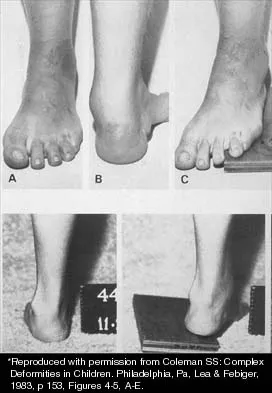

Question 23

A 15-year-old boy with a type I hereditary sensory motor neuropathy (Charcot-Marie-Tooth disease) reports recurrent ankle sprains and significant pain in the hindfoot and midfoot despite orthotic management. Examination reveals that he walks with a drop foot and has dynamic clawing of the toes. Clinical photographs of the left foot are shown in Figure 7. Management should consist of

Explanation